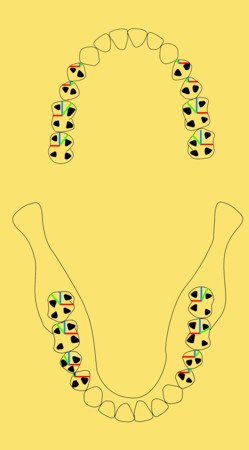

Primera Parte RESUMEN: La alta complejidad inherente a los procedimientos de Rehabilitación Oral, obligan al profesional que la ejerce a basarse en parámetros multidisciplinarios, a veces lo suficientemente intrincados que hacen imposible la práctica de la misma, sin la presencia en su mente de una clara concepción de la Oclusión. The extreme complexity of Oral Procedures, make it imperative for the working professional to rest on multidisciplinary parameters, sometimes so complex that make impossible its practice without the presence of a clear idea of Oclusion. DESARROLLO Suele ser sumamente árido el abordaje de un tema como Oclusión, desde la perspectiva de nuestro diario trabajo ,con todo el strees que este conlleva, con toda la lucha que significan citas, honorarios, diferentes personalidades de los pacientes, inquietudes de los mismos, etc. «LA MEJOR OCLUSIÓN ES LA QUE TIENE LA MEJOR DESOCLUSIÓN» Básicamente, podemos como desde hace ya muchos años se viene haciendo; clasificarlos en: A)Determinantes Posteriores (fijos) Más contemporáneamente, en: I-Mecanismos Primarios: A.T.M. GUIA ANTERIOR INCLINACIÓN DEL PLANO OCLUSAL CURVA SAGITAL DE SPEE FORMA DE LA ARCADA III-Mecanismos Elementales CRESTAS TRIANGULARES INTERNAS Analicemos cada uno de ellos: Es evidente, que la reproducción de las características de la A.T.M., en nuestro aliado fundamental, el Articulador; es imprescindible. Partiendo de la premisa de obtener una OCLUSIÓN MUTUAMENTE PROTEGIDA, para luego arribar al concepto de OCLUSIÓN MUTUAMENTE COMPARTIDA, concepto este que desarrollaremos durante el transcurso de las distintas entregas, analizaremos cada uno de los FACTORES DETERMINANTES DE LA OCLUSIÓN. El primero de ellos, por ser fijo e invariable, solo diremos que: son sus INCLINACIONES PLANARES, o sea : A-INCLINACIÓN DE LA TRAYECTORIA CONDILEA C-BENNET INMEDIATO articuladores totalmente ajustables) D-DISTANCIA INTERCONDILAR. En cuanto a la GUÍA ANTERIOR, mecanismo primario y por supuesto anterior, provee al cuerpo mandibular; del camino a recorrer durante las excursiones protrusivas y lateralidades, a través del vínculo entre las piezas dentarias anteriores, superiores e inferiores. En un corte sagital, podemos observar la relación entre estos donde vemos que se vinculan sin entrar en un contacto franco, sino más bien en una relación de vencindad muy intima a la que llamamos: PUNTO DE ACOPLAMIENTO. Otros factores fundamentales de la GUÍA ANTERIOR son : A-ALTURA FUNCIONAL B-PUNTO DE ACOPLAMIENTO En cuanto a los SURCOS, sabemos que durante una Transtrusión, las cúspides fundamentales generan surcos sobre las piezas que antagonizan. Dichos surcos proveen de una vía de escape a las cúspides antagonistas para evitar colisiones, con las indeseables fuerzas laterales cuya gravedad ya conocemos. MECANISMOS SECUNDARIOS La CURVA FRONTAL DE WILSON, se observa invertida a nivel de los caninos y de los primeros premolares. El PLANO OCLUSAL, en realidad no es ningún plano, sino la sumatoria de muchos MICROPLANOS, los cuales individualmente pueden constituir factores presentes en la OCLUSIÓN, pero auténticos problemas para la DISCLUSIÓN. La CURVA SAGITAL DE SPEE, denominada originariamente de BALKWIL-SPEE, fue concebida como una curva. El cuarto factor SECUNDARIO: el ANCHO DE LA ARCADA, es evidente que variando los ejes de rotación , alrededor de las diferentes distancias ;cambiará la dirección de los escapes (surcos), de los elementos que en el se muevan (cúspides). MECANISMOS ELEMENTALES Los CUATRO NIVELES DE OCLUSIÓN y las CRESTAS TRIANGULARES INTERNAS, constituyen de por si, la herramienta ejecutora de las funciones gnáticas. A- ELEVACIONES 1-Puntas Cuspídeas B-DEPRESIONES 1-Fosas SURCOS DE DESARROLLO De las CRESTAS TRIANGULARES INTERNAS, acentuamos su importancia en ellas dado que son las efectoras finales de la molienda, y su triangularidad debe tener su base partiendo del surco y su vértice terminando en la Punta Cuspídea, condición importante para evitar colisiones durante la transtrusión (movimiento de lateralidad ). EFECTOS DE LA VARIABILIDAD DE LOS FACTORES DETERMINANTES DE LA OCLUSÍON Cada uno de los determinantes influye aumentando o disminuyendo tanto la DESOCLUSIÓN como la ALTURA CUSPÍDEA INCLINACIÓN DE LA TRAYECTORIA SAGITAL INCLINACIÓN DEL PLANO OCLUSAL RADIO DE CURVATURA DE LA ÁNGULO DE LA TRAYECTORIA ALTURA DEL PUNTO DE LATERO SURTRUSIÓN / MOV. DE BENNET INMEDIATO CURVA FRONTAL DE WILSON SURCOS BIBLIOGRAFÍA Dibujos y esquemas tomados del libro: Oclusión Orgánica…un camino hacia la Rehabilitación Oral. 1)William Mc Horris,B.S.,D.D.S. Oclusión. Con especial énfasis sobre :El rol funcional y parafuncional de los dientes anteriores. 2)Von Spee , Craff(Anatomista alemán, describió la curva de compensación de la articulación de molares y premolares).CURVA DE SPEE 1.89 3)Stuart,D.»Some aspects of the inervation teeth.»Procedings of Royal Society of Medicine.20:1675,19274)Muhleman,H. y Savdir,S»Tooth movility-its causes and significance»Journal of Periodontology ,36:153,Marzo ,Abril,1965. 4)Muhleman,H. Y Savdir,S»Toothmovility its causes and significance» Journal of Periodontology,36:153,marzo,abril,1965. 5-Oclusión y Diagnóstico en Rehabilitación Oral. 6-Anatomia Odontológica. -A contribution to the study of the movementes of the mandible. 8-Celenza F.W, Nadeskin J.F.,Oclusión.Situación actual. 9-D´Amico 10-Dawson P.E. 11-Huffman -Regenos. 12-Hobo S.-Takayama H.A. 13-Lucia V.O 14-Mc Horris. 15-Mc Horris. 13-Posselt U. 16-Stuart C. 17-Vartan Veshnilian

CUATRO NIVELES DE LA OCLUSIÓN

De los primeros diremos que podemos dividirlos en:

2-Rebordes(Marginales y Transversos)

2-Surcos (de Desarrollo y Suplementarios)

CRESTAS CENTRALES REBORD.MARGINALES

Los surcos de Trabajo (ST)en rojo, No Trabajo (SNT) en verde, y Propulsión (SP) en azul, provéen de vías de escape a las cúspides durante la Transtrusión.